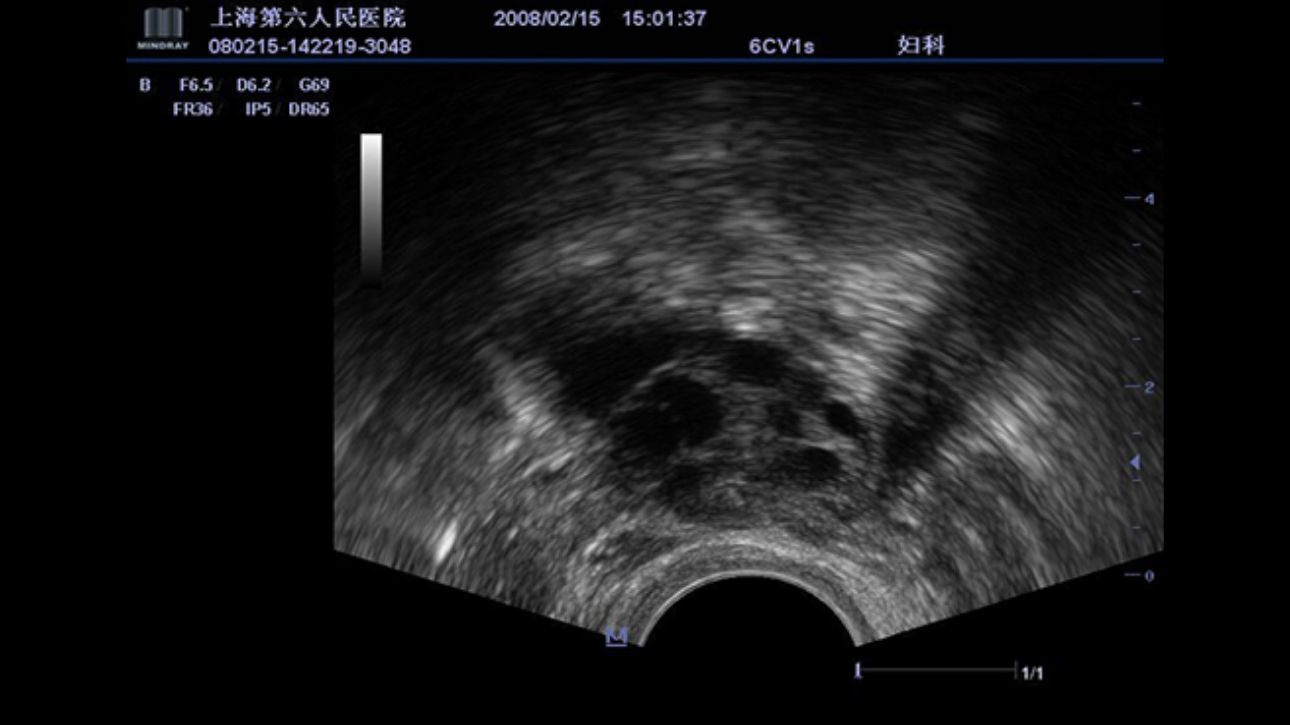

A fully-featured laptop style color Doppler system, M5 offers uncompromised 2D performance and exceptional value in a highly convenient and easy to use package. Equipped with advanced technologies such as Smart 3D TM and efficient workflow software, makes M5 ideal for use within obstetrics and gynecology application field.

Performance

PSHITM(Phase Shift Harmonic Imaging)

Purified Harmonic Imaging for better contrast resolution providing clearer images with excellent resolution and less noise.

iClearTM(Speckle Suppression Imaging)

Gain improved image quality based on auto structure detection